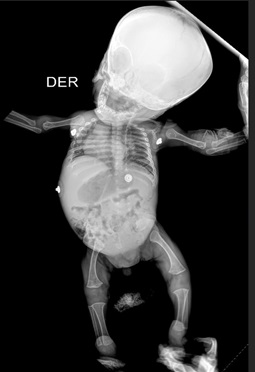

Antecedentes: considerando que la acondroplasia es una enfermedad perteneciente a un grupo de displasias, según la literatura actual conocido como un proceso poco frecuente, con secuelas permanentes y con necesidad de evaluaciones continuas para mejorar capacidad funcional y tratar de manera oportuna sus complicaciones. Reporte de caso: se presenta un caso clínico de Acondroplasia, atendido la E.S.E Hospital Departamental Universitario del Quindío, San Juan de Dios (Colombia), se trata de un paciente de sexo masculino de 11 meses de edad de nacionalidad venezolana, con pobre red de apoyo familiar, esquema incompleto de vacunación, sin antecedentes familiares ni patológicos de importancia referidos por la madre; el cual ingresa a la institución por síntomas respiratorios con posterior evolución a falla ventilatoria, falla cardiaca aguda y alto riesgo de mortalidad, dadas sus características morfológicas se sospecha por examen físico alta probabilidad de displasia ósea, razón por la cual se solicita intervención multidisciplinaria y manejo por endocrinología pediátrica quien confirma diagnóstico clínico y paraclínico de acondroplasia congénita, sin confirmación genética. Conclusión: en el caso expuesto, se evidencia cómo la desigualdad social, ausencia de afiliación a empresas prestadoras de salud (EPS) y privación del seguimiento clínico son factores que aumentan probabilidad de complicaciones y dificulta la atención integral de los pacientes.